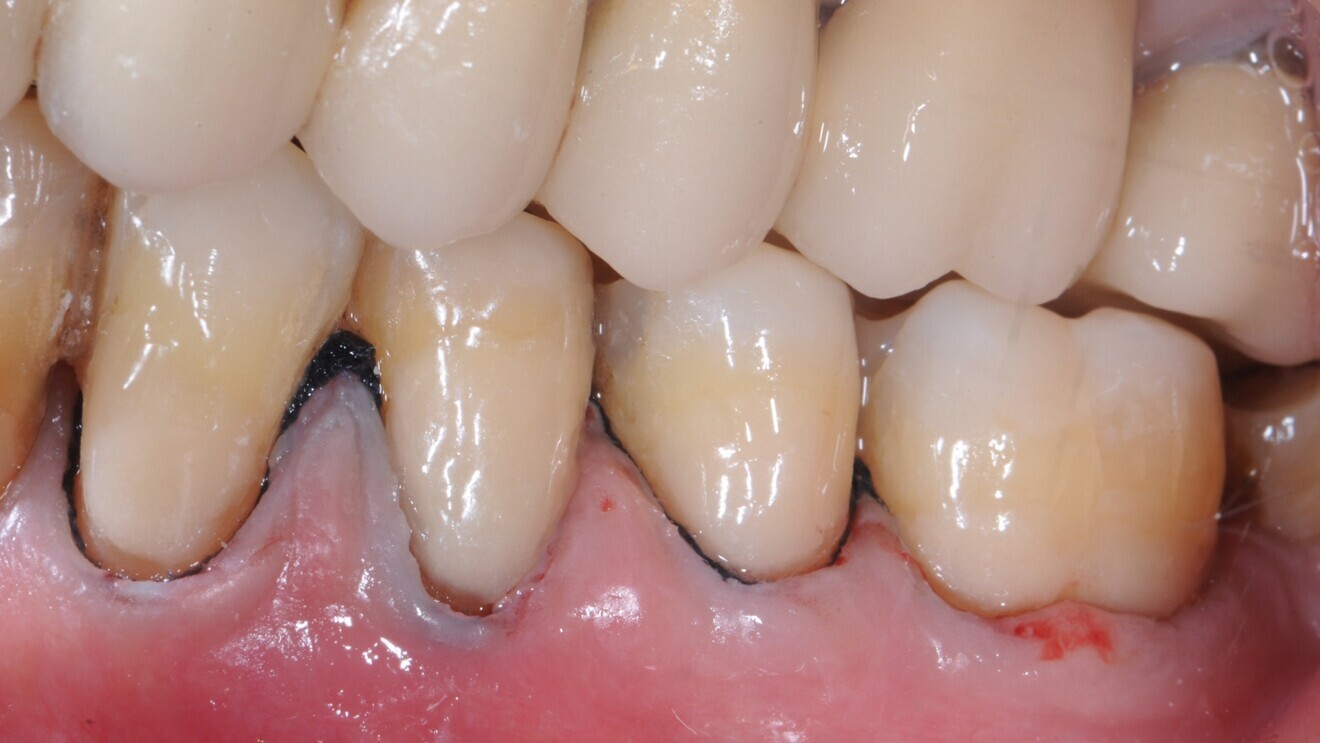

Fig. 2: Cervical lesions restored with the glass hybrid EQUIA Forte.

Fig. 3: Glass hybrid restorations at follow-up after 6.5 years.

The first study included a small sample of 25 patients with non-carious cervical lesions and bruxism.6 In these overall rather young patients, 148 lesions were randomly restored, indicating a massive clustering of the lesions per patient, with either a glass hybrid (EQUIA Forte, GC) or a resin composite (ceram.x one universal, Dentsply Sirona). After six, 12 and 24 months of follow-up, the restorations were re-evaluated using the modified United States Public Health Service (USPHS) criteria. When assessing the 126 remaining restorations in 22 patients at the 24-month recall, it was apparent that both materials had performed similarly. Only for marginal adaptation was a significant difference found, the glass hybrid showing slightly reduced adaptation. Secondary caries was not observed on any of the restorations.

Another study, with a follow-up of 36 months, assessed the survival, quality and costs of glass hybrid (EQUIA Forte) and resin composite restorations (Filtek Supreme XTE, 3M) for managing sclerotic non-carious cervical lesions.7 In 88 patients (50–70 years of age) with 175 lesions, restorations were placed directly without any mechanical preparation, which eventually resulted in high annual failure rates for both groups. Restoration quality was assessed at one, 18 and 36 months using the FDI World Dental Federation criteria. Costs were evaluated using a micro-costing approach (accounting for the time for material placement) and, during follow-up, fee items of the statutory insurance in Germany. Of the 88 patients, 43 received the glass hybrid (83 restorations) and 45 received the resin composite (92 restorations); cluster randomisation had been applied. At 36 months, 17 glass hybrid restorations and 19 resin composite restorations showed total retention loss, and five glass hybrid restorations had been partially lost. There was no significant difference between the materials. The FDI ratings were not significantly different for any domain except surface lustre. Here, the composite restorations were superior to the glass hybrid ones, although it should be noted that the latest generation of glass hybrids address such aesthetic effects. Costs were significantly lower for the glass hybrid restorations—both initially (€32.57; SD: €16.36) and in the long term (€41.72; SD: €25.08)—compared with the resin composite restorations (€51.60; SD: €26.17).

In summary, both studies—randomised trials of a robust design—indicate the suitability of glass hybrids for restoring cervical lesions. Moreover, they not only demonstrate that the material shows similar survival, but also flag the advantageous cost-effectiveness of this material. That glass ionomer materials work well for this indication is not necessarily new. However, aspects concerning the economic differences between composites and glass hybrids for managing cervical lesions had not been assessed in detail before. Regardless of the restorative material used, preparation of sclerotic surfaces is likely beneficial.